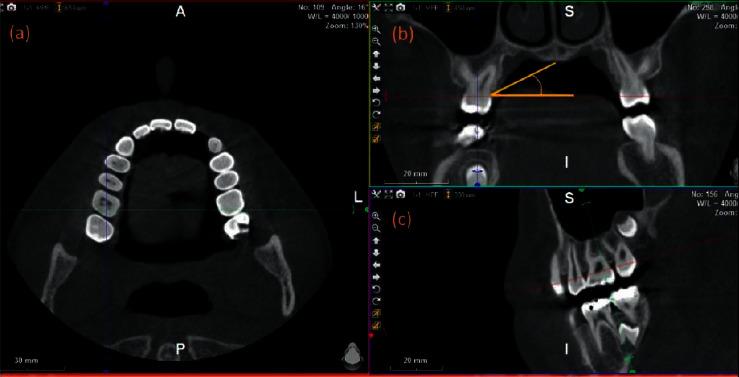

METHODS

Out of 1,737 CBCT images, fifty-six images met the inclusion criteria and were included in this cross-sectional study. The palatal vault angle on the maxillary first molar was measured and divided the images into 3 groups. The soft tissue thickness between the maxillary first premolar and second molar was measured at a distance of 3, 6, 7, 8, and 9 mm from the cementoenamel junction. All the image measurements were performed using CBCT-viewer software.

分析锥形束计算机断层扫描(CBCT)图像中的腭部软组织厚度,并评估组织厚度与腭穹窿角度之间的关系。

方法

在1737张CBCT图像中,56张图像符合纳入标准并被纳入本横断面研究。测量上颌第一磨牙处的腭穹窿角度,并将图像分为3组。在上颌第一前磨牙和第二磨牙之间,从牙釉质牙骨质界3、6、7、8和9毫米处测量软组织厚度。所有图像测量均使用CBCT-viewer软件进行。